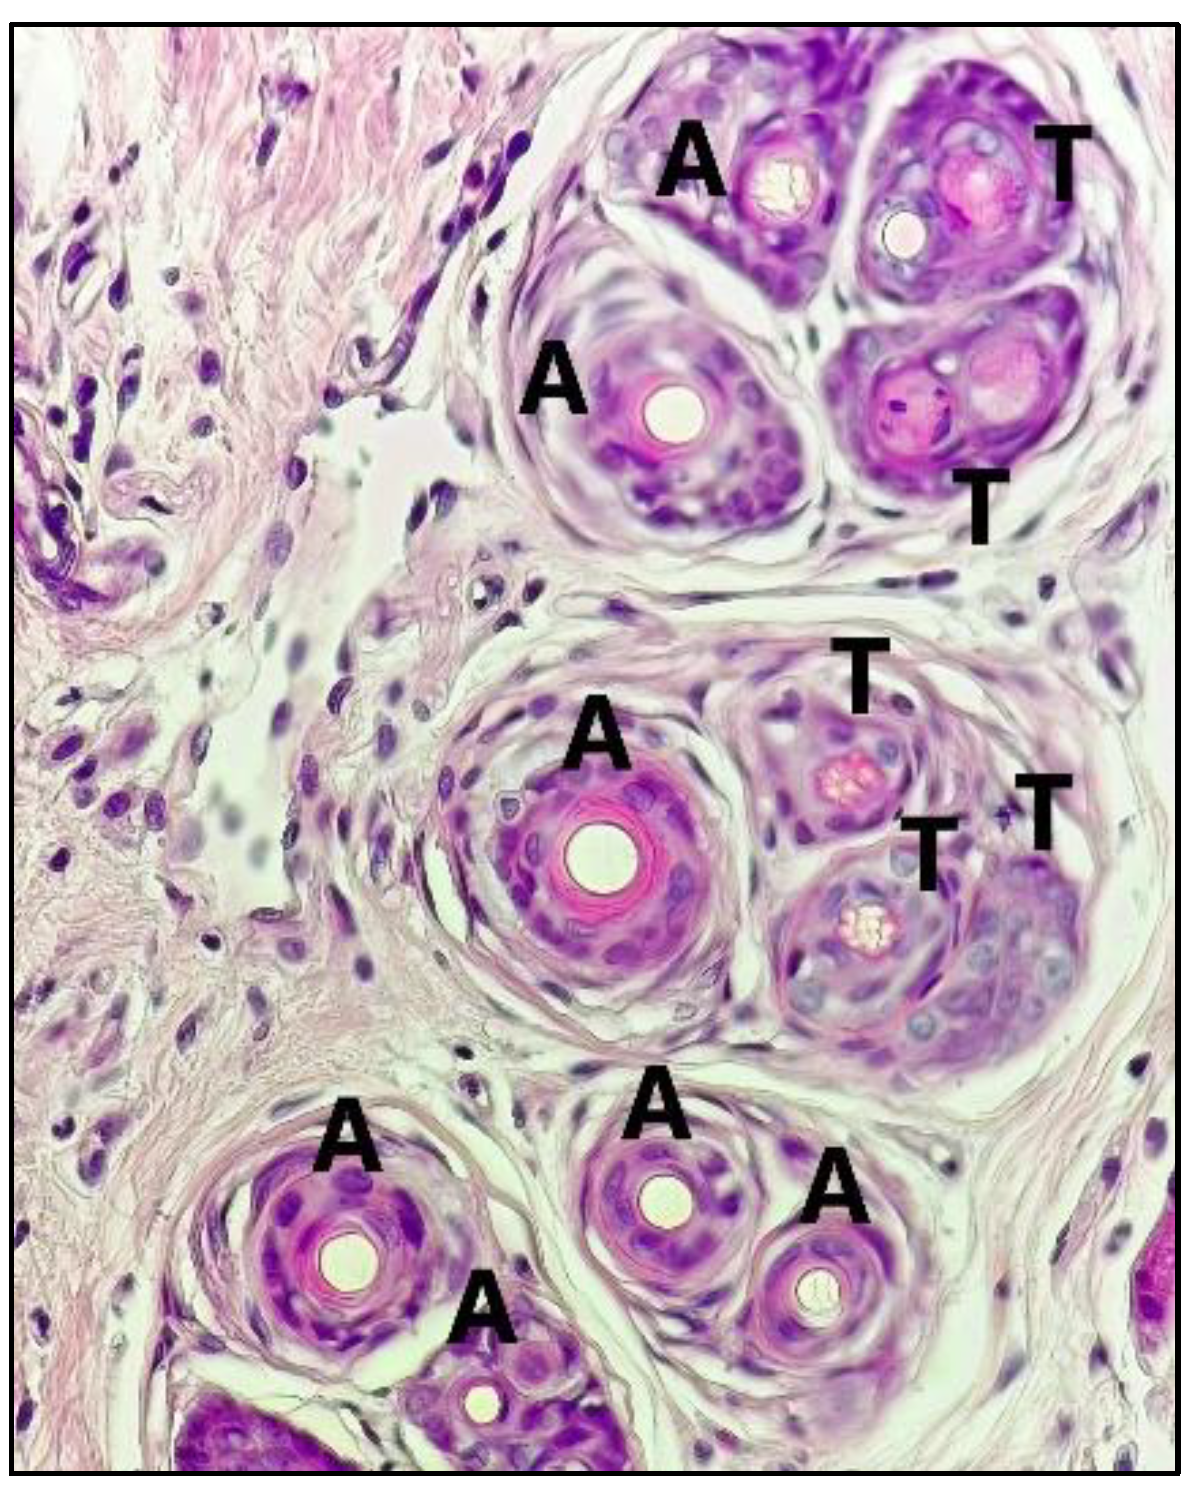

| Stage | Group | Treatment | Hair Follicular Density | Total of Hair Follicular Density | A/T Ratio | |

|---|---|---|---|---|---|---|

| Anagen | Telogen | |||||

| Fraction | I | DHT (s.c.)+vehicle (NaCMC 1%) | 12.55 ± 0.38 | 19.00 ± 1.53 | 31.55 ± 1.64 * | (1/1.50) |

| II | DHT (s.c.)+Minoxidil | 46.56 ± 1.17 | 33.56 ± 0.19 | 80.12 ± 1.02 ** | (1.39/1) | |

| III | DHT (s.c.)+FW 25% | 39.67 ± 0.67 | 29.45 ± 0.69 | 69.12 ± 1.35 ** | (1.35/1) | |

| IV | DHT (s.c.)+FEA 25% | 49.78 ± 0.51 | 27.00 ± 0.33 | 76.78 ± 0.84 ** | (1.84/1) | |

| V | DHT (s.c.)+FH 25% | 16.78 ± 0.88 | 25.33 ± 0.33 | 42.11 ± 1.07 * | (1/1.68) | |

| Sub-fraction | VI | DHT (s.c.)+FEA-1 25% | 23.33 ± 1.07 | 26.33 ± 1.00 | 49.66 ± 0.33 * | (1.13/1) |

| VII | DHT (s.c.)+FEA-2 25% | 18.22 ± 1.07 | 14.67 ± 0.88 | 32.89 ± 1.71 * | (1.24/1) | |

| VIII | DHT (s.c.)+FEA-3 25% | 48.44 ± 1.17 | 29.55 ± 0.38 | 78.00 ± 1.52 ** | (1.64/1) | |

| IX | DHT (s.c.)+FEA-4 25% | 28.00 ± 0.58 | 23.22 ± 1.26 | 51.22 ± 1.68 * | (1.21/1) | |

| X | DHT (s.c.)+FEA-5 25% | 25.89 ± 1.17 | 27.56 ± 0.51 | 53.45 ± 1.39 * | (1/1.06) | |

| XI | DHT (s.c.)+FEA-6 25% | 21.55 ± 0.38 | 37.55 ± 0.69 | 59.11 ± 1.07 * | (1/1.74) | |